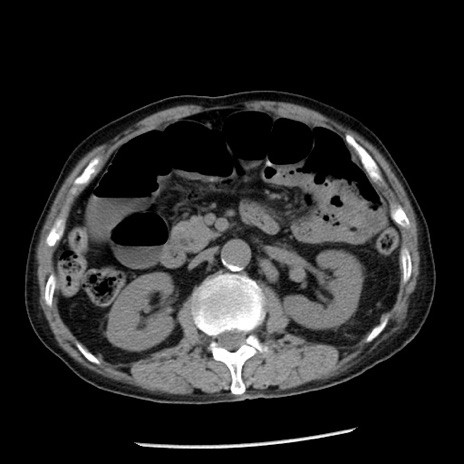

冠状断像

【症例】80歳代男性

【主訴】嘔吐

【現病歴】昨晩2回嘔吐あり、今朝になっても嘔吐あり。来院。

【既往歴】胃潰瘍

【身体所見】意識清明、BT 37.6℃、BP 166/95mmHg、HR 100bpm、SpO2 97%、腹部:平坦・軟、腸蠕動音聴取良好、圧痛なし。

【データ】WBC 21900、CRP 1.46